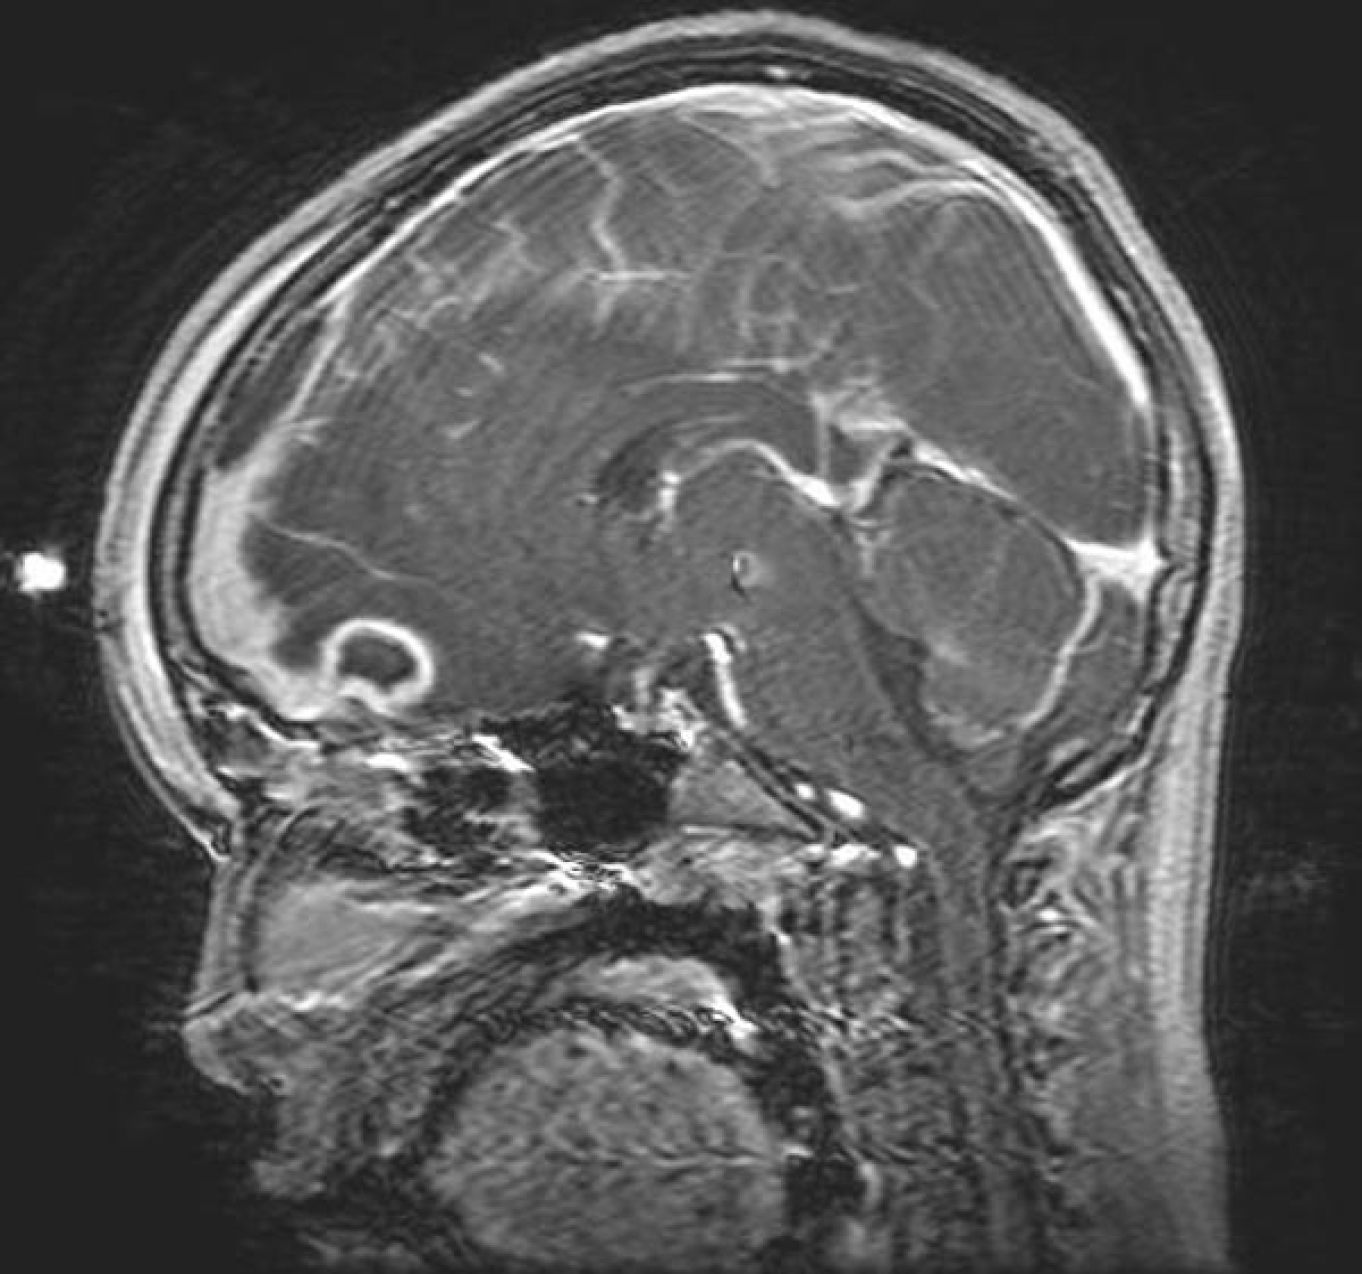

Because of the risk of intracranial extension and the potentially nonspecific symptoms that could accompany empyema formation, abscess development, or cerebritis, practitioners should maintain a high index of suspicion for central nervous system complications. With this in mind, practitioners should obtain three-dimensional imaging for any patients presenting with fever, headache, and forehead swelling or ear proptosis. Contrast is essential for identifying rim-enhancing abscesses or empyemas. Computed tomography generally is favored in the initial characterization of mastoiditis (because of the better definition it provides when evaluating the structures of the temporal bone), while magnetic resonance imaging is preferable for identifying intracranial empyema and abscess formation. (See Figures 5 and 6.)

Figure 5. Pott's Puffy Tumor on Magnetic Resonance Imaging |

![]() |

Source: Radswiki. Pott's puffy tumor 004. Published May 31, 2008. https://upload.wikimedia.org/wikipedia/commons/0/01/Potts-puffy-tumor-004.jpg CC BY-SA 3.0 |